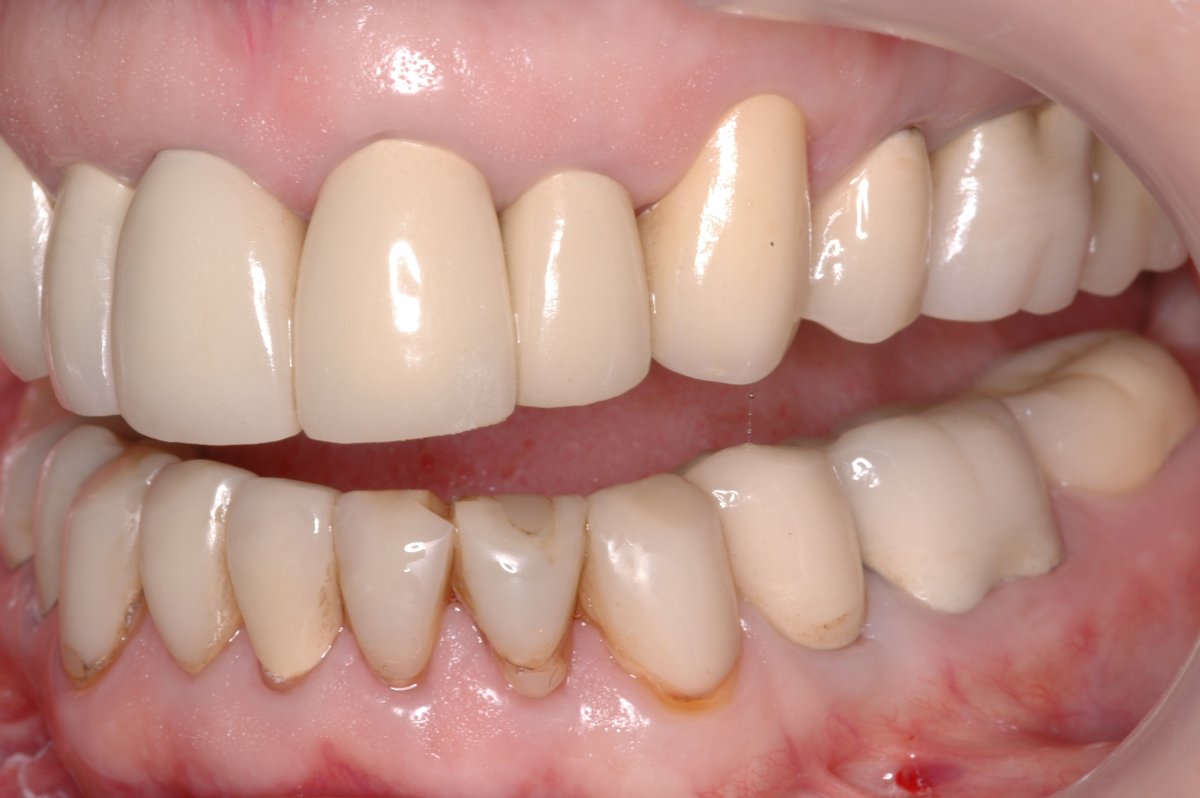

FullMouth Restoration Before & After. This patient received a full Dental Rehabilitation With Zirconia This study revealed that zirconia implants have been more prominent in the last ten years, which is a valuable option. Regarding the use of zirconia for isfcdps, the 2018 iti consensus report stated that “implant This clinical report describes a complete mouth. Zirconia is a suitable choice for prosthetic rehabilitation in crowns and veneers due to its white color, adaptability,. Dental Rehabilitation With Zirconia.

Full Mouth Rehabilitation with Zirconia Crowns Dental Rehabilitation With Zirconia The dental ceramic with the highest reported mechanical properties is zirconia. This clinical report describes a complete mouth implant rehabilitation with computer. Zirconia is a material widely used in fixed prosthodontics, whether on natural teeth or on implants, with excellent results over time. Regarding the use of zirconia for isfcdps, the 2018 iti consensus report stated that “implant This clinical. Dental Rehabilitation With Zirconia.

Case 3, Comprehensive Rehabilitation with Zirconia Crowns InHouse Dental Rehabilitation With Zirconia This study revealed that zirconia implants have been more prominent in the last ten years, which is a valuable option. The dental ceramic with the highest reported mechanical properties is zirconia. Zirconia is a suitable choice for prosthetic rehabilitation in crowns and veneers due to its white color, adaptability, exceptional fracture resistance, and flexural. This clinical report describes a complete. Dental Rehabilitation With Zirconia.